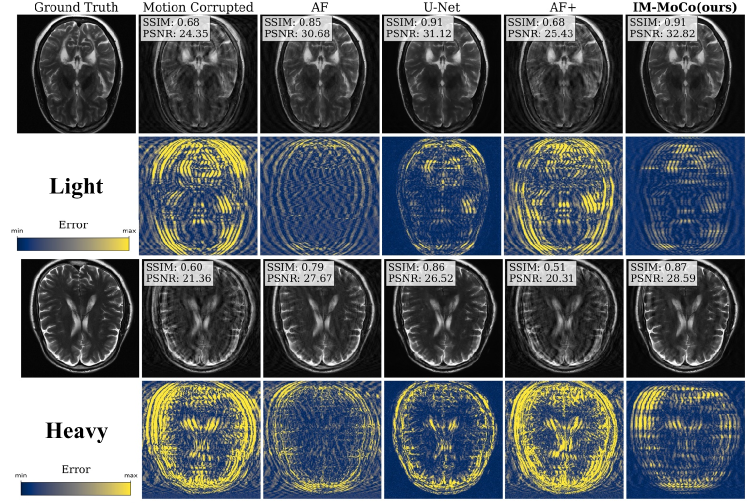

Refer to caption

Figure 3: k𝑘klD-Net detection results. The first and second show the detection performance of the k𝑘kLD-Net for light and heavy motion, respectively.

Figure 4: The visualization shows the worst results of motion-corrected images of our IM-MoCo pipeline besides motion-corrupted, ground truth, and comparison methods. The first and third rows show the light and heavy correction results, respectively. The second and fourth rows show the residual error images.

Figure 5: The visualization shows the best results of motion-corrected images of our IM-MoCo pipeline besides motion-corrupted, ground truth, and comparison methods. The first and third rows show the light and heavy correction results, respectively. The second and fourth rows show the residual error images.